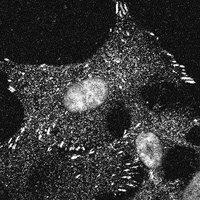

If we want BCIs that can last a lifetime in the human brain, we need to fund the science that explains why they currently don’t. Link to basicscience resources:

🛣️ BCIs will Run Out of Runway "... The X-Ray is pretty good, and so is penicillin, and neither were discovered with a practical objective in mind. I mean, when the electron was discovered in 1897,...